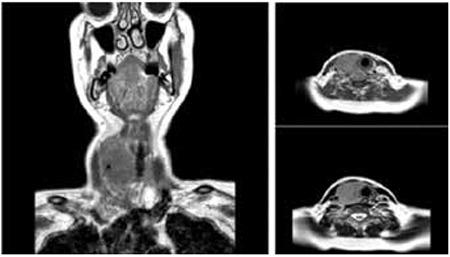

Rapidly Growing Thyroid Mass: An Unusual Case of Acute Lymphoblastic Leukemia.

https://cdn.ncbi.nlm.nih.gov/pmc/blobs/5684/4563207/4fbd18109e81/TJH-32-276-g1.jpg